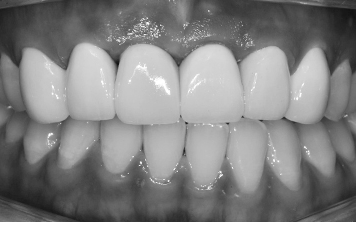

대화할 때, 웃을 때 바로 보이는 앞니는 조금만 어색해도 인공치라는 느낌이 바로 드러납니다. 앞니 임플란트는 자연치와 구분되지 않는 섬세한 디자인이 핵심입니다. 퍼펙트치과는 앞니 치료에 특화되어있어 색상, 위치, 각도를 조절해 자연스러운 미소를 만듭니다.

앞니 임플란트의 완성도는 잇몸 라인에서 차이가 납니다. 기성품이 아닌 맞춤형 지대주를 사용해 잇몸 뼈와 형태까지 고려한 전치부 임플란트를 설계합니다.